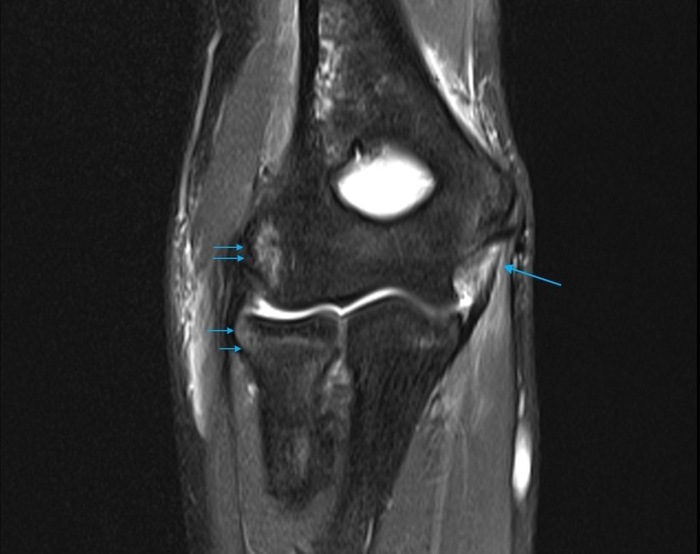

- МРТ - когда нужно дополнить УЗИ, оценить наличие отека костного мозга.

- МРТ - более обширная картина сустава, включая определение отека костного мозга.

МРТ - обычно малоинформативно

- МРТ - более точный метод диагностики, позволяет оценить состояние мягких тканей и костной ткани, увидеть отек кости, заподозрить остеомиелит.

Инфекционный артрит с остеомиелитом.